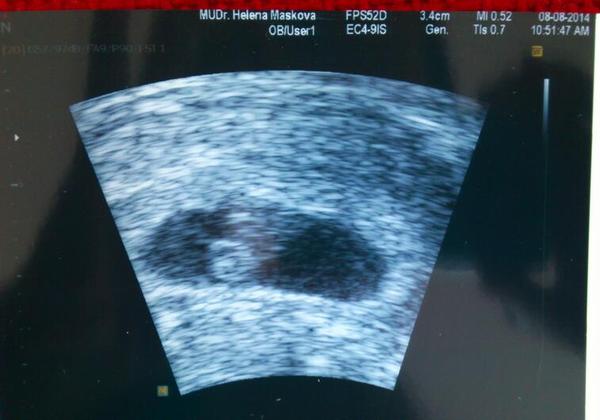

2.7.2014 - kontrola vše OK, sliznice11,5, vpravo 8 folíků, 5 větších 3 mají kolem 18, vlevo 7 folíků, také pár kolem 18, končím stimulaci, večer v 21 píchnout pregnyl 7500